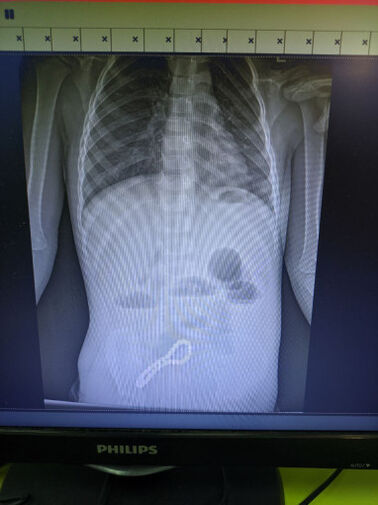

Врачи Рязанской областной клинической больницы спасли трехлетнего мальчика, который проглотил магнитный браслет. Об этом сообщили в пресс-службе регионального минздрава.

Ребенок попал в больницу с жалобами на проблемы с пищеварением. Медики предположили наличие в ЖКТ инородного тела, что подтвердил рентген.

«Было принято решение об операции. Мы провели минилапаротомию (хирургическое вмешательство, при котором через разрез передней брюшной стенки производится доступ к внутренним органам живота). И увидели, что магнитами, которые притянулись друг к другу, соединены петли кишки; в ее стенке отверстия. В ходе операции удалили все 30 магнитных бусин: 29 маленьких и одну большую», — рассказал хирург больницы Олег Ларькин.